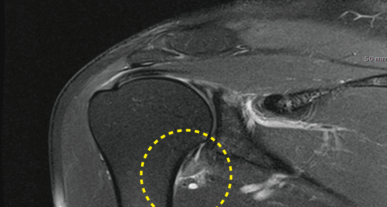

2) 동결견 초기에는 회전근 개 질환과 구별이 어려울 수 있지만, 시간이 지날수록 뚜렷한 차이가 나타납니다. 또한, 견갑 흉곽 운동이 주로 나타나면서 움직임에 "덜컹" 거리는 느낌이 생길 수 있습니다.

물리 치료에도 불구하고 증상이 심한 경우 수술적 치료가 고려될 수 있습니다. 관절경술은 관절내 생리 식염수 주입, 이상 병변 제거술, 세척술 등을 통해 관절낭을 팽창시키고 동반된 병변을 조사하여 적절한 치료를 시행할 수 있습니다. 이는 임상에서 확인되지 못한 병변을 발견하는 잇점이 있습니다.